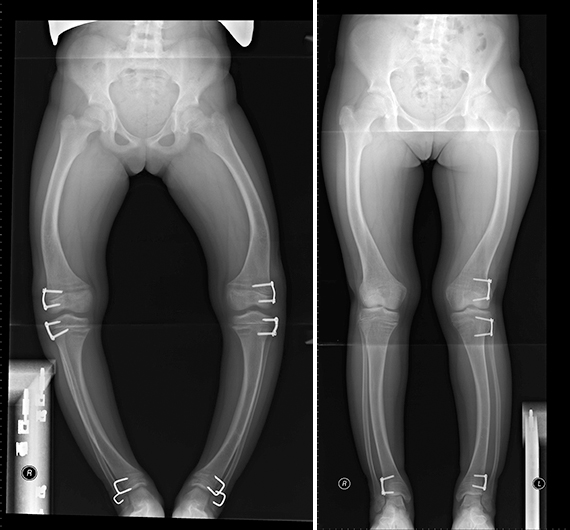

Аппарат Илизарова: принцип работы и применение

Раздел: Моменты озарения